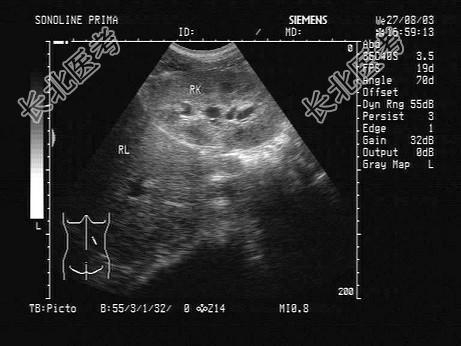

- 单项选择题某患者,既往有肾炎病史。因头晕, 无尿三日入院,根据其肝右叶-右肾声像图, 以下最可能的诊断为 ( )

B、慢性肾衰